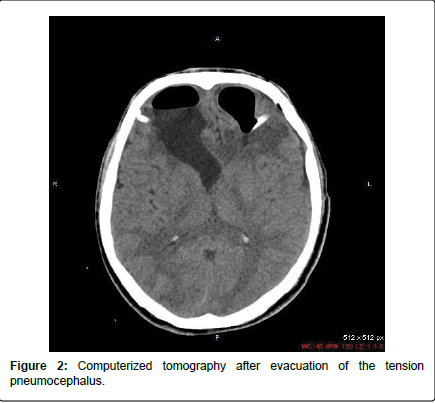

late sign of increased intracranial pressure